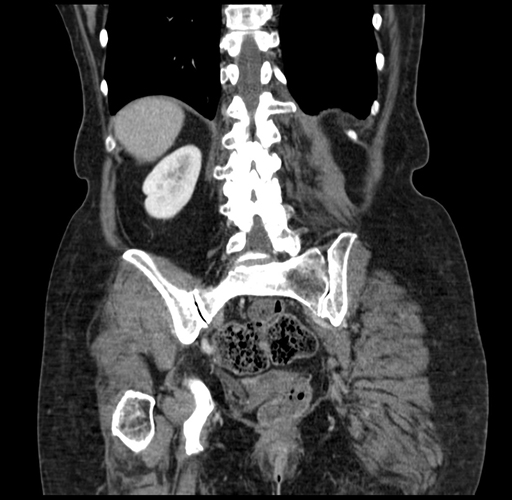

Pre-Chemo: Coronal Venous

Coronal Venous